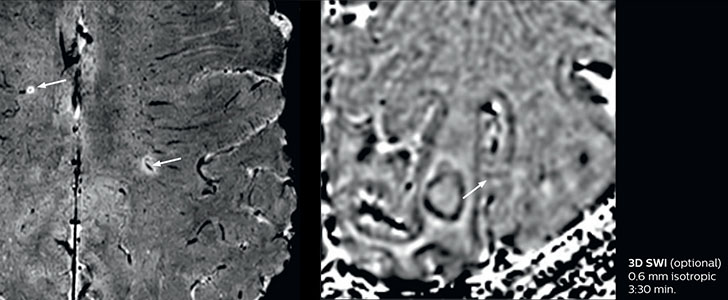

The abbreviated MS protocol for brain is only around 9 minutes, so in case of suspected multiple sclerosis, one or two more advanced sequences may be added, such as PSIR (phase sensitive inversion recovery) or susceptibility-weighted sequences to help us make more confident diagnoses in these inflammatory cases.

In this example, the optional 3D multishot susceptibility weighted sequence with 0.6 mm isotropic voxels is 2 lesions with a central vein sign (arrows) and one lesion with a phase-rim sign (arrowhead). The total scan time, including SmartBrain and axial PD/T2 3mm, is 11:10 min. and is 18:30 min. with the optional 3D PSIR and 3D SWI multishot included.

“We used to have long examination times for certain types of patients, a few lasting more than 40 minutes,” says Dr. Savatovsky. “What is remarkable, is that now all these examinations are below 30 minutes, which opens up opportunity to add more sequences when needed. It’s really hard to keep a patient for more than 40 minutes in the scanner, but because we have now cut scan times by at least 10 minutes, we can add more sequences without making the exam too long. And this is where the new system helps us make a difference. Examples include our examinations for informing brain tumor classification or giant cell arteritis workup, or for intracranial wall imaging – so in patients where we need several advanced sequences or high resolution sequences.” “We added three additional sequences in our brain neoplasm classification exam: a 3D SWI sequence, APT and ASL on top of 3D morphologic sequences, an isotropic DSC (dynamic susceptibility contrast) and multivoxel spectroscopy. I think that in patients that need a classification for brain mass, for example, we can provide a more detailed and confident diagnosis than before, allowing the clinicians to decide for either a medical workup if no tumor is suspected, or for neurosurgery as soon as possible if a neoplasm is suspected.” “In multiple sclerosis patients, we increasingly include a multishot susceptibility sequence [3] in our routine cases, thanks to the shorter scan times. Our abbreviated MS protocol for brain is around 8 to 9 minutes, so we can ask for one or two additional sequences to visualize the central veins, or to get an additional contrast to better depict posterior fossa lesions. In cases of white matter lesions of unknown significance on FLAIR images, for example when we see high signal hyperintensities in the brain, we can add on more advanced sequences such as PSIR (phase sensitive inversion recovery) or susceptibility-weighted sequences to help us in distinguishing between MS and nonspecific or vascular abnormalities in these inflammatory cases.”